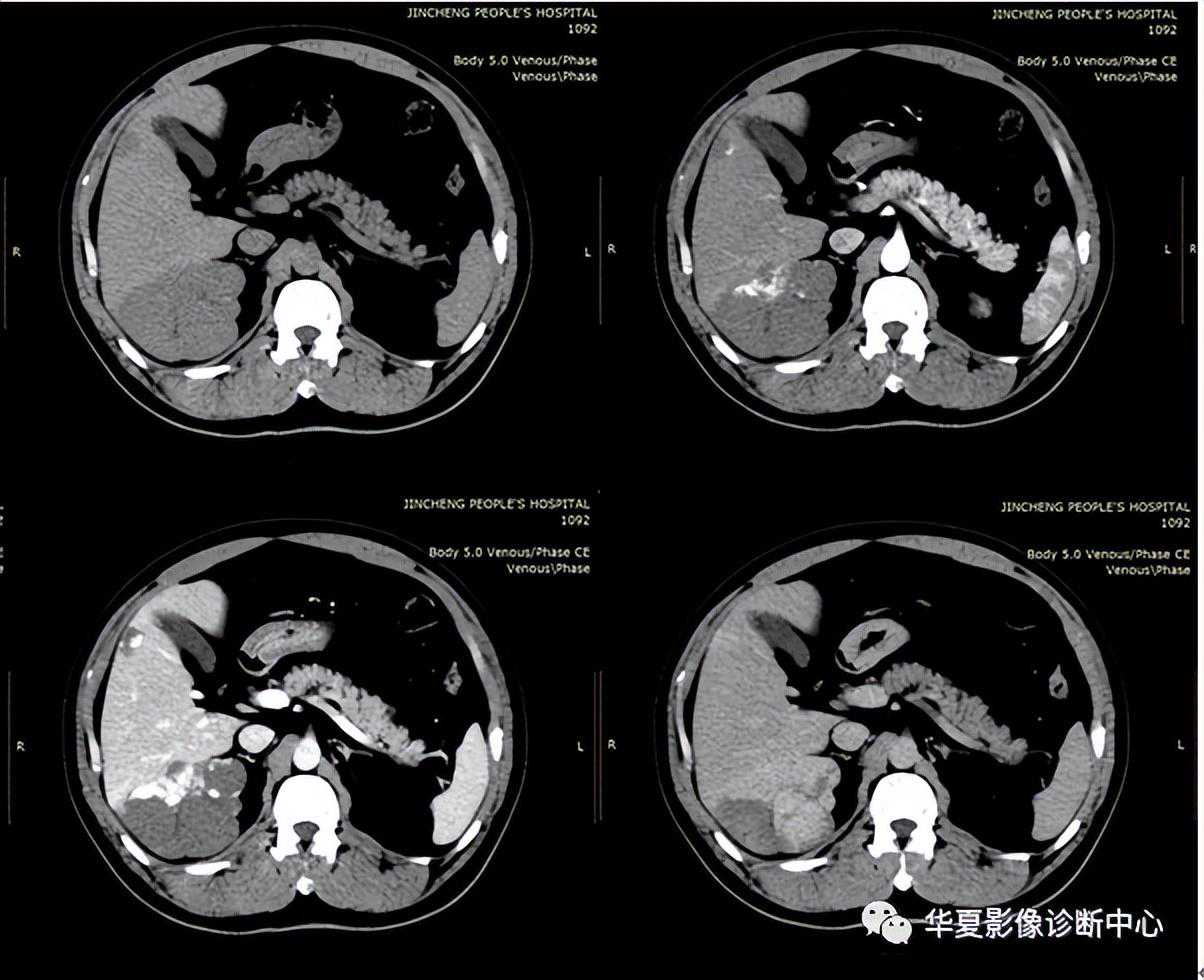

高密度环征是指在压痛部位结肠旁可见与结肠壁相连的肿块,近似于乳腺密度,中心密度较低,边缘密度较高,邻近脂肪间隙模糊,局部腹膜增厚。此为炎症导致增厚的脏层腹膜。组织病理显示致病的肠脂垂外脏层腹膜覆盖纤维白细胞渗出物。肠脂垂见于腹水CT。肠脂垂因扭转或自发性静脉血栓而梗死,继发炎症反应,称为原发性肠脂垂炎,区别于因周围器官病变导致的继发肠脂垂炎。原发性肠脂垂炎的影像表现具有特异性,可以明确诊断。CT显示结肠周围1-4cm的脂肪密度团块周围2-3mm高衰减环。偶尔有高衰减中心,此为栓塞的血管及出血坏死。

鉴别诊断包括继发肠脂垂炎和网膜梗死。结肠憩室炎是继发肠脂垂炎最常见的原因,需通过有无临近憩室、结肠壁增厚脓肿除外,多普勒超声有助于炎症和梗死的区别。网膜梗死常更大(3.5-7cm),蛋糕状,预后与原发性肠脂垂炎相。肠脂垂附于结肠带,特别是沿独立带和网膜带的两侧,多见于盲肠和乙状结肠,为许多大小不等、形状不定的脂肪小突起,它是由肠壁浆膜下的脂肪组织集聚而成。每个肠脂垂通过一个狭窄的短蒂供血,这个带蒂的特点及较大的活动性大大增加了扭转及梗死机率,从而导致局部缺血引起炎症和四周水肿。由于脂垂分部广泛,患病部位可自盲肠至乙状结肠,疼痛部位亦随之变化,压痛最明显的部位即病变脂垂所在部位,重者可有反跳痛及肌紧张,较少见,不易与急性阑尾炎、乙状结肠憩窒炎及某些妇科疾病相鉴别。